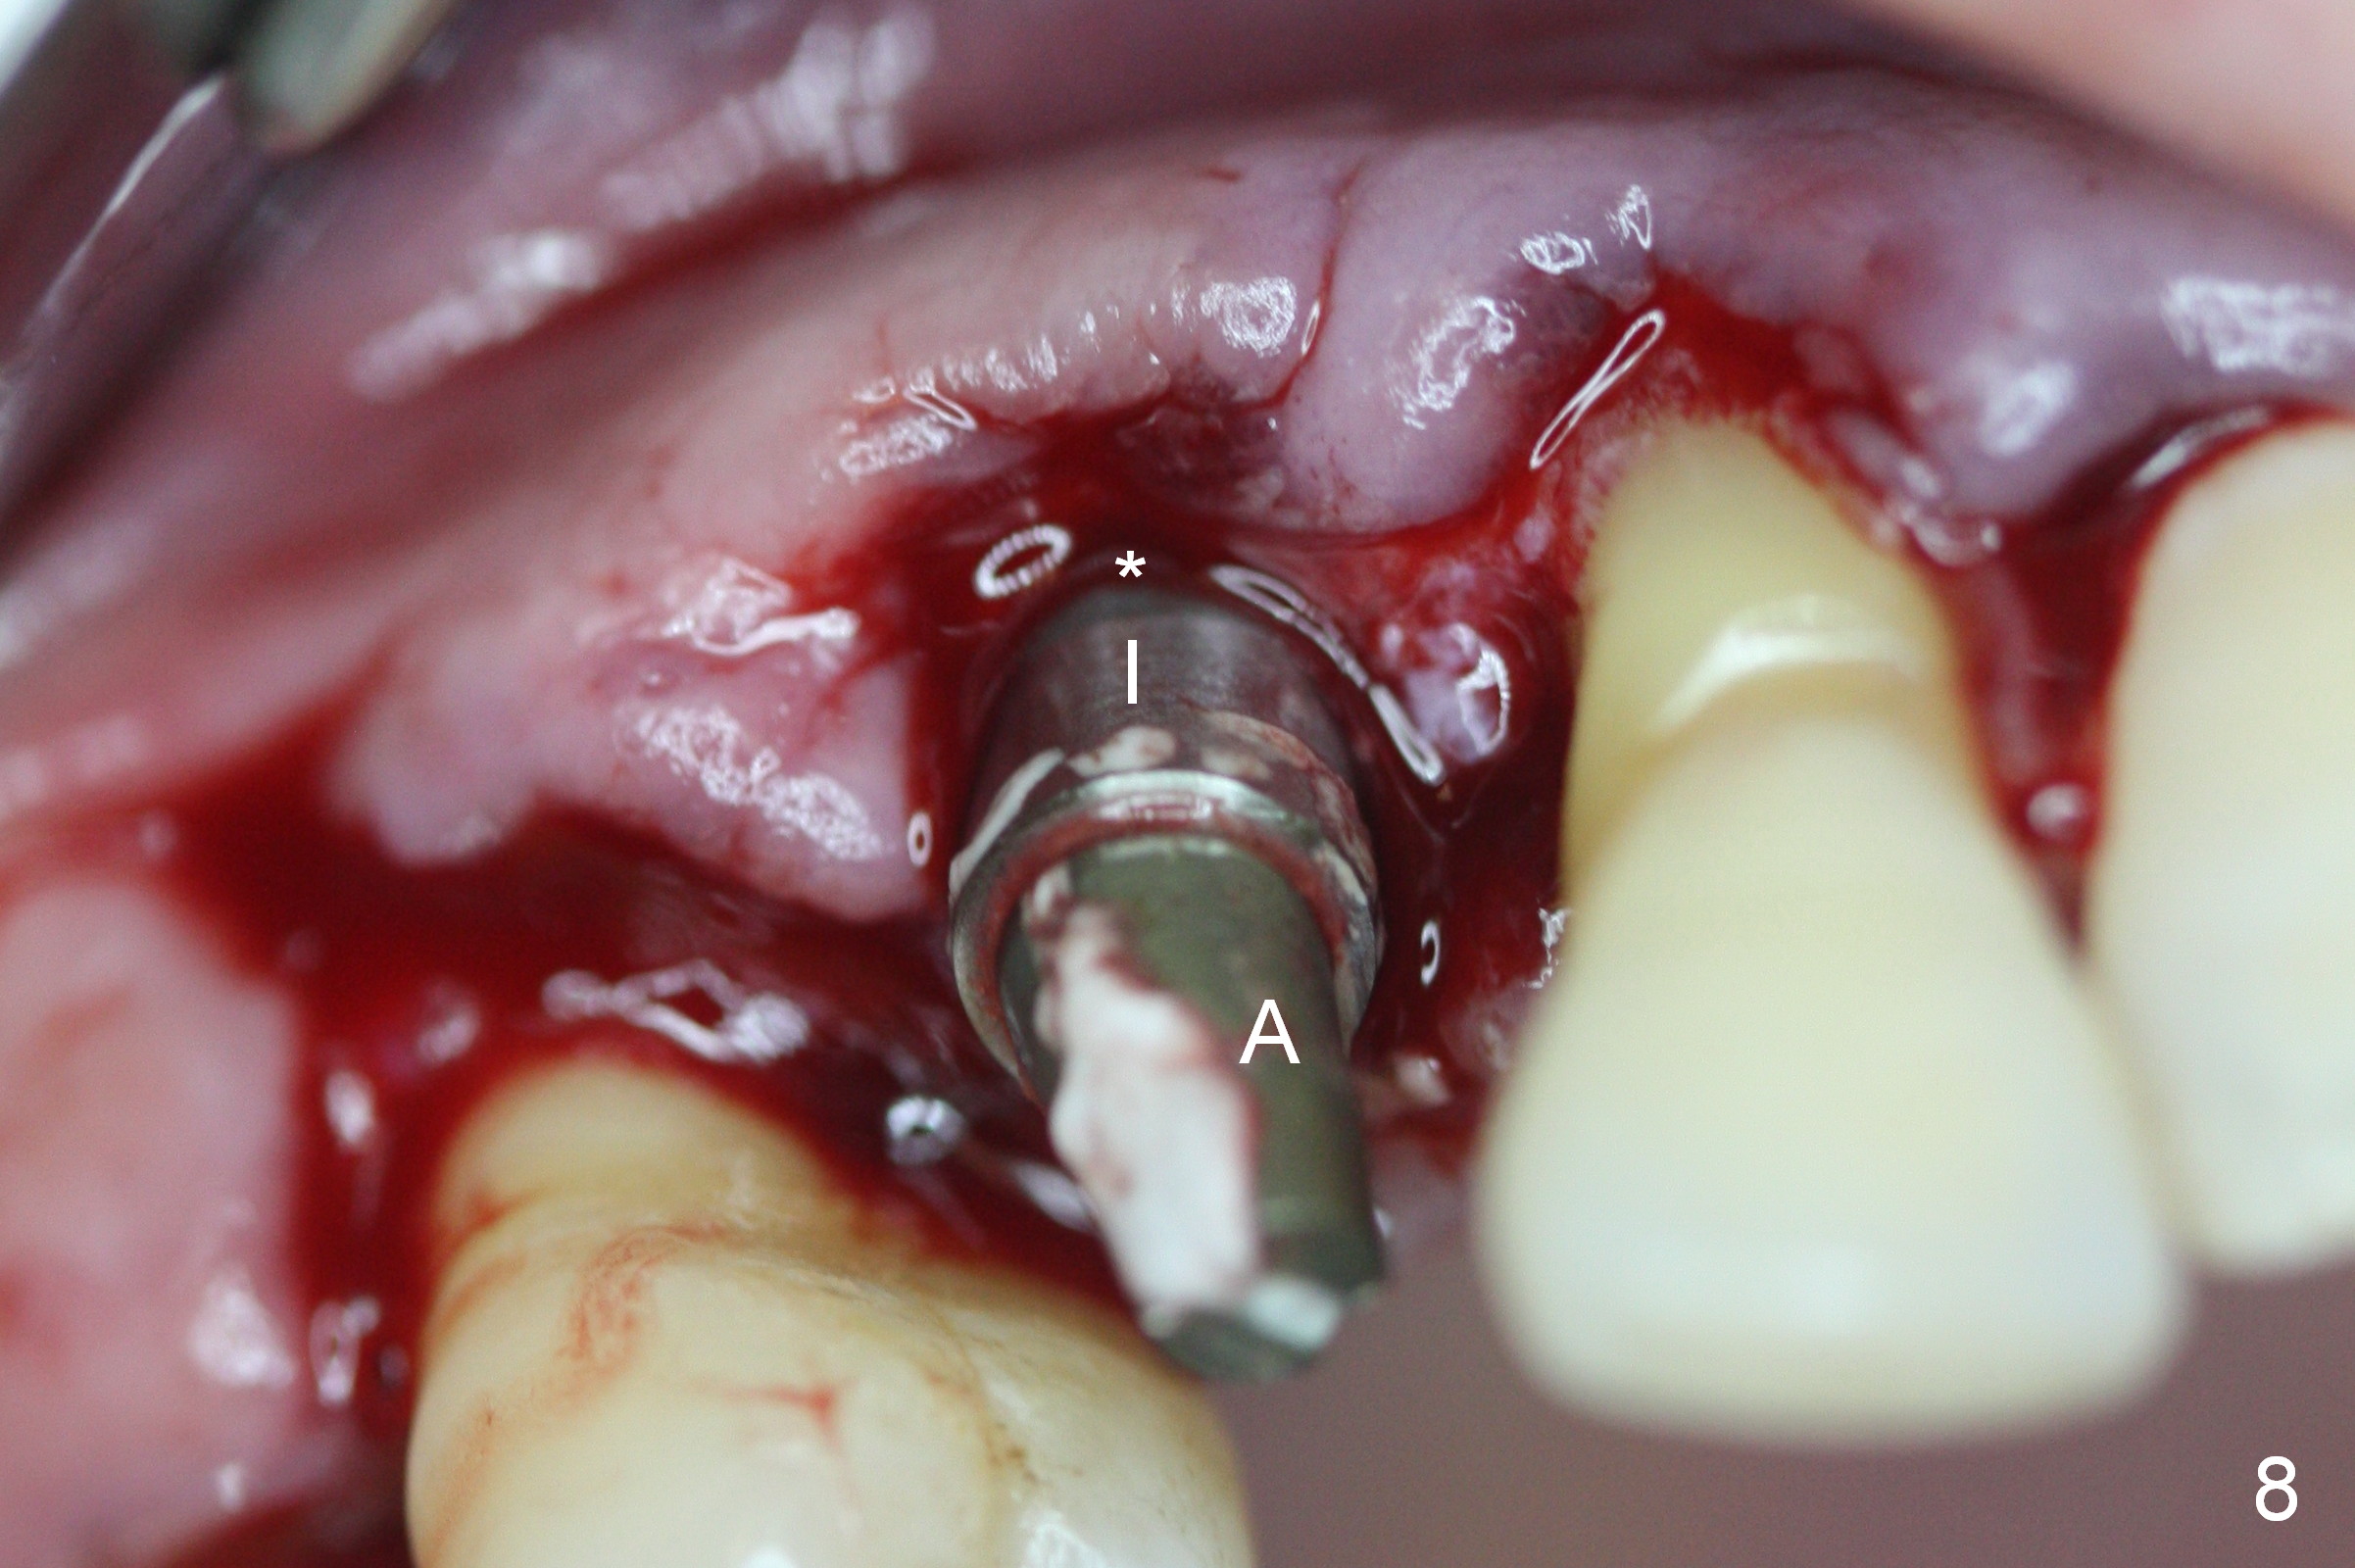

Four months post implant placement, the immediate provisional (Fig.1 P) has mobility with tenderness and perforation at the cervix (^). When the provisional is removed, the buccal plate bulging is more evident (Fig.2 arrowheads). The latter is apparently caused by bone expansion associated with implant placement (Fig.3 black *), since the bulging is not so obvious in a preop CBCT 3 D image (Fig.4 *). There is a layer of fiber granulation tissue (Fig.3 white *) around the mobile implant (I). More fiber tissue is noted when the implant is removed (Fig.5). A new osteotomy is created in the palatal wall of the existing implant site with 2 mm pilot drill, followed by 2.5 and 3 mm reamers. As a 4.5x17 mm tap is being inserted (Fig.6 T), it is deviated buccally. Reamers are re-used to try to remove more palatal bone to let the implant be placed more palatally. When a 4.5x17 mm tissue-level implant is placed (Fig.7,8 I with insertion torque >60 Ncm), there is a small buccal gap (Fig.8 *). A 20° angled abutment (Fig.7,8 A) is placed. An immediate provisional is fabricated with cosmetic satisfaction.